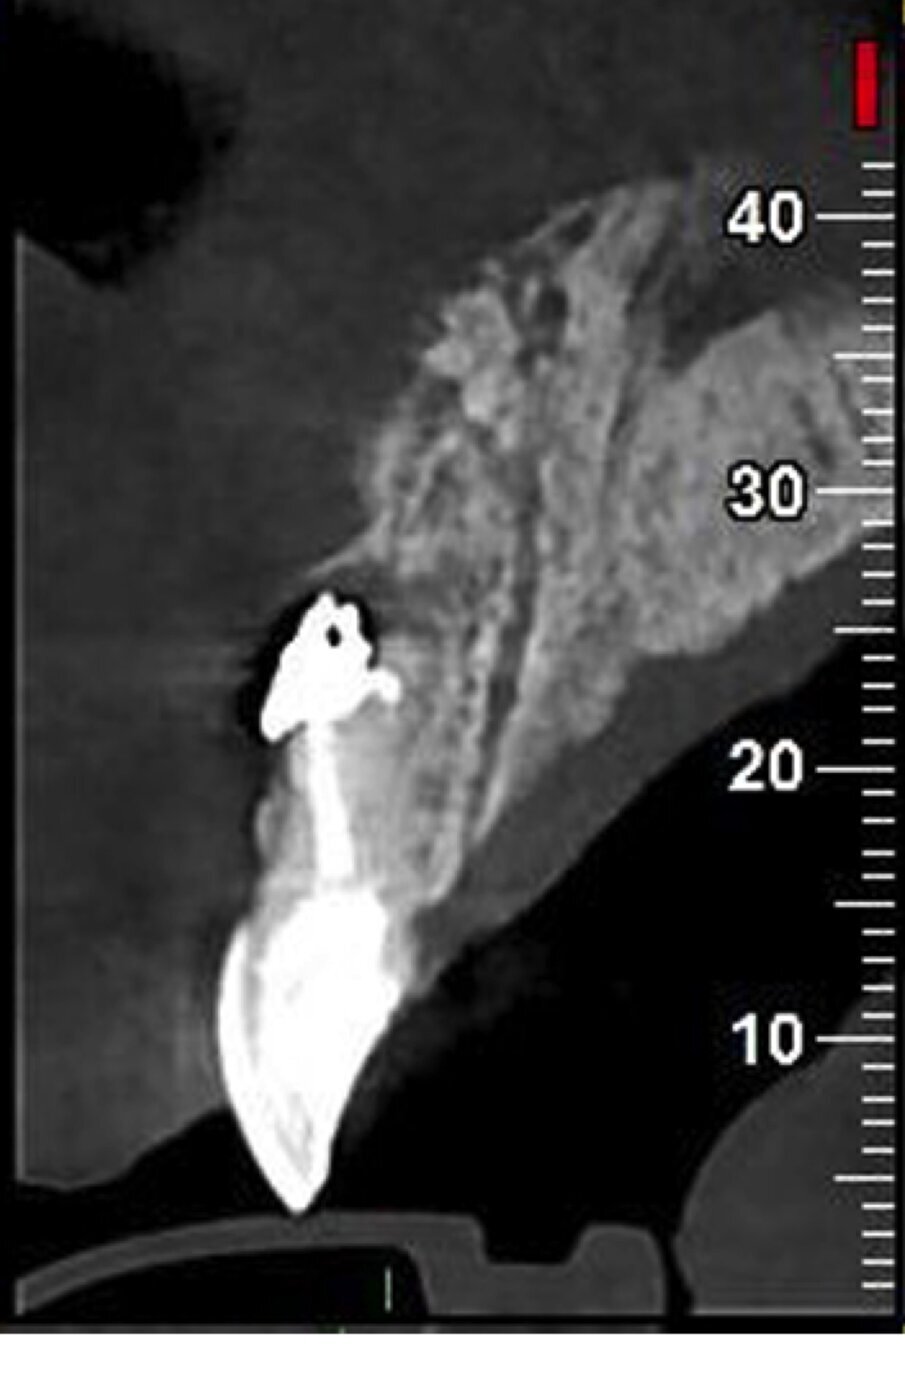

Nei primi mesi del 2016, tuttavia, il paziente perde l’impianto in sede 22, ha fastidio nel settore frontale e nota un “brufolino”, ma per il professionista è tutto a posto. Non convinto, l’insegnante effettua una consulenza da un altro odontoiatra e scopre che il dente 11 ha dei problemi. È compromesso da un processo infettivo cronico (area di rarefazione radiograficamente evidenziabile) con evidenza radiografica e una fistola, prima inesistente. C’è una perforazione iatrogena della radice del dente, con sbuffo di materiale radiopaco nel parodonto.

In parole semplici il paziente scopre che la terapia è stata mal eseguita e ha prodotto un danno (falsa strada). Risulta necessario un secondo intervento ortogrado e retrogrado da parte di uno specialista in endodonzia dal costo di 850 euro. Ai controlli successivi le problematiche rientrano. Il giovane insegnante protesta con il primo odontoiatra, chiede indietro quanto ha speso per il trattamento del dente 11 (ossia 250 euro) e per l’intervento endodontico di recupero del dente, 850 euro, per un totale di 1.100 euro.